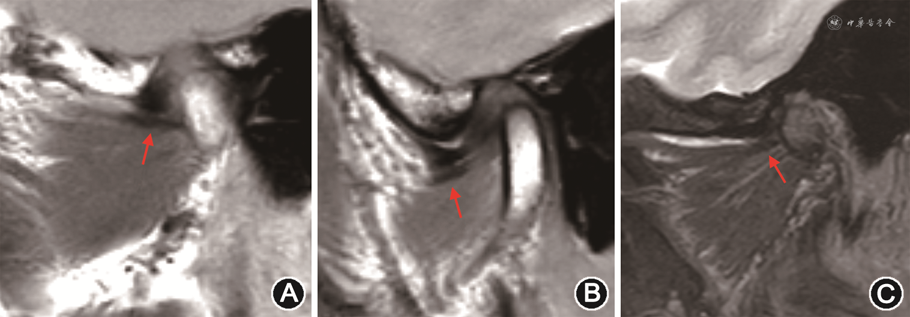

正常翼外肌上头肌腱在PDWI图像上呈管状均匀低信号(图3A),下头肌腱呈扁平线状均匀低信号(图3B)[14];需要注意的是,Ⅲ型的中间部分的肌腱是由上头底部和下头顶部两束肌腱组成,位于附着点偏外侧份,在PDWI图像上信号与关节盘相仿,易误认为关节盘前移位[7]。肌腱断裂或部分撕裂,是慢性退变和(或)炎症最严重的后果,表现为肌腱纤维全部或部分信号不连续,PDWI及T2信号增高,完全断裂肌腱呈挛缩表现(图3C),部分可见腱鞘周围积液,PDWI及T2WI-FS上呈高信号;增强扫描可见强化[14]。